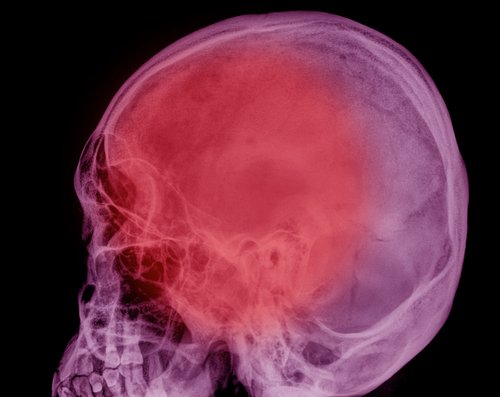

Empty sella syndrome (ESS) merupakan gangguan pada sella tursika, struktur tulang di dasar otak yang mengelilingi dan melindungi kelenjar pituitari. ESS biasanya sering ditemukan saat melakukan tes pencitraan radiologis untuk gangguan hipofisis. Pada ESS, sella tursika terisi dengan sebagian cairan serebrospinal dan kelenjar hipofisis yang sangat kecil yang terletak di dasar sella atau terisi penuh oleh cairan serebrospinal tanpa kelenjar hipofisis yang terlihat. Kebanyakan individu yang mengalami ESS tidak mengalami gejala, tetapi akan menimbulkan kekhawatiran akan kekurangan hormon.

Diagnosis ESS dibuat berdasarkan beberapa identifikasi dari gejala karakteristik, riwayat pasien secara rinci, evaluasi klinis pasien secara menyeluruh dan teknik pencitraan khusus seperti pemindaian tomografi terkomputerisasi (CT-scan) dan pencitraan resonansi magnetik (MRI).

- Penggunaan CT-scan. Tes ini dilakukan dengan menggunakan sinar-X dan komputer untuk membuat gambar tubuh.

- Penggunaan MRI. Tes ini menciptakan tampilan 2-D dari organ atau struktur internal tubuh Anda, terutama otak atau sum-sum tulang belakang.